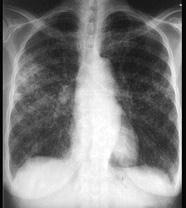

问题 女,23岁,消瘦盗汗1月余,干咳1周,偶痰中带血,影像如图,最可能的诊断为 ( )

选项 A、慢性支气管炎 B、SLE肺部侵犯 C、含铁血黄素沉着 D、弥漫性肺纤维化 E、粟粒性肺结核

答案 E